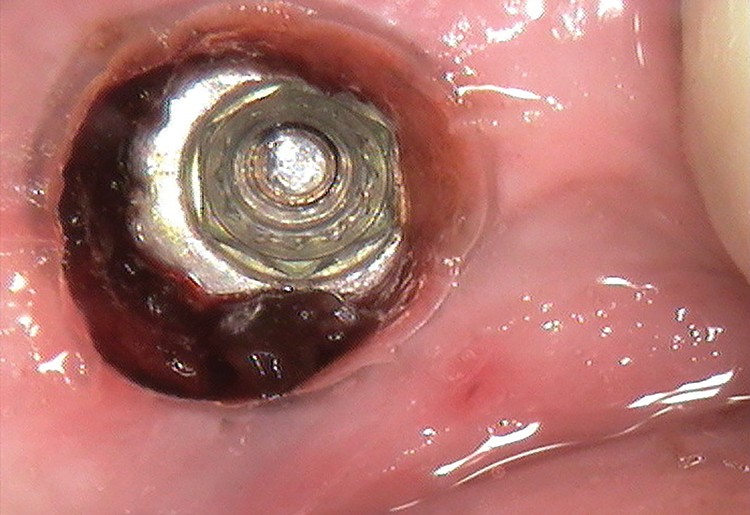

(4.) View of the screw fragment after the fixture was uncovered with a biopsy punch.

Figure 4

(5.) View of the screw fragment after a 10-minute soak with tartar and stain remover solution.

Figure 5

Once anesthesia was achieved, a periodontal probe was used to identify the extent of the implant platform, and then an appropriately sized biopsy punch was used to access the implant (Figure 4). Following access, a presoak of tartar and stain remover was injected into the fixture for a period of 10 minutes. This helped to remove any debris and corrosive elements that may have contributed to the difficulty of retrieval (Figure 5). A 0.36-mm capillary suction tip was used to remove the solution, and a new volume was deposited to penetrate the fixture as needed.